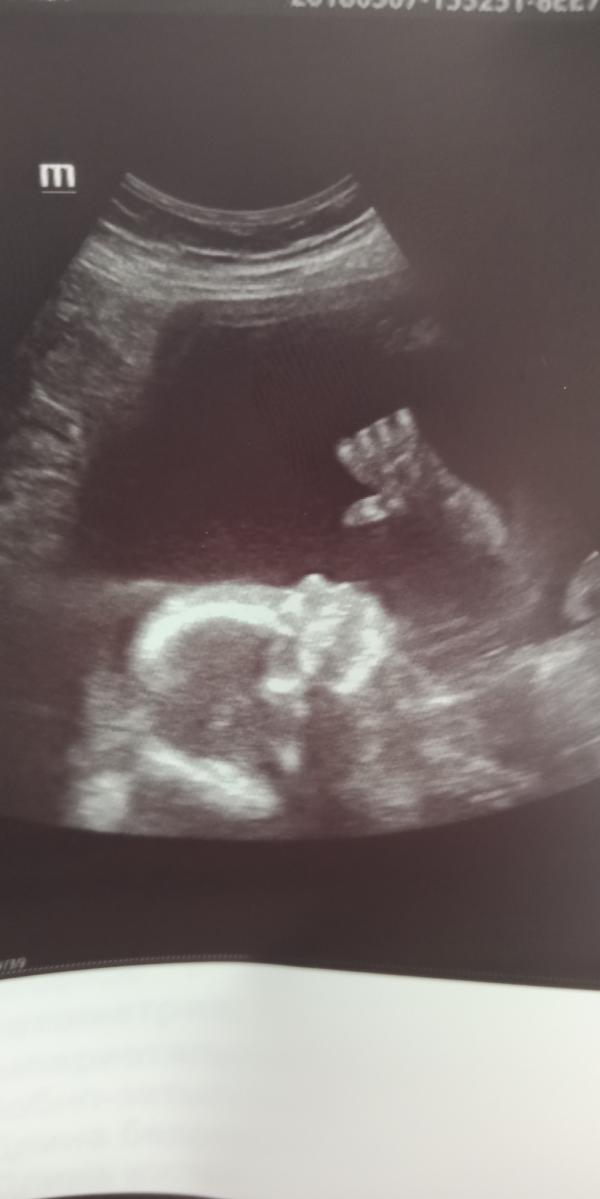

@hig2910city я то по началу думала девочка, пинается не сильно, скромная, а на УЗИ как показал свои пречендалы)))

И как будто лежал позировал)

@aavolobu этот снимок с планового))) ещё на 21 недели))